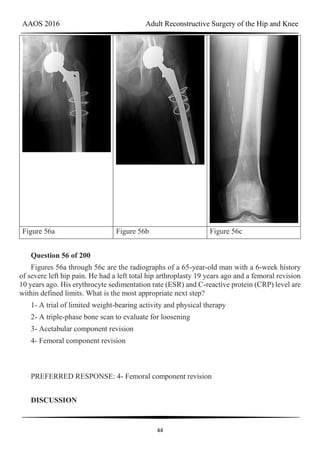

Figure 56a Figure 56b Figure 56c

Question 56 of 200

Figures 56a through 56c are the radiographs of a 65-year-old man with a 6-week history

of severe left hip pain. He had a left total hip arthroplasty 19 years ago and a femoral revision

10 years ago. His erythrocyte sedimentation rate (ESR) and C-reactive protein (CRP) level are

within defined limits. What is the most appropriate next step?

1- A trial of limited weight-bearing activity and physical therapy

2- A triple-phase bone scan to evaluate for loosening

3- Acetabular component revision

4- Femoral component revision

PREFERRED RESPONSE: 4- Femoral component revision

DISCUSSION

AAOS 2016 Adult Reconstructive Surgery of the Hip and Knee

45

The radiographs reveal a fracture of the extensively porous coated stem. This entity,

although rare, is associated with higher risk for occurrence when thin stems are implanted in

patients with thick cortices and there is a lack of proximal stable support for the prosthesis.

Nonsurgical care likely would not help this patient. A triple-phase bone scan would not add

any information that would change the treatment plan.